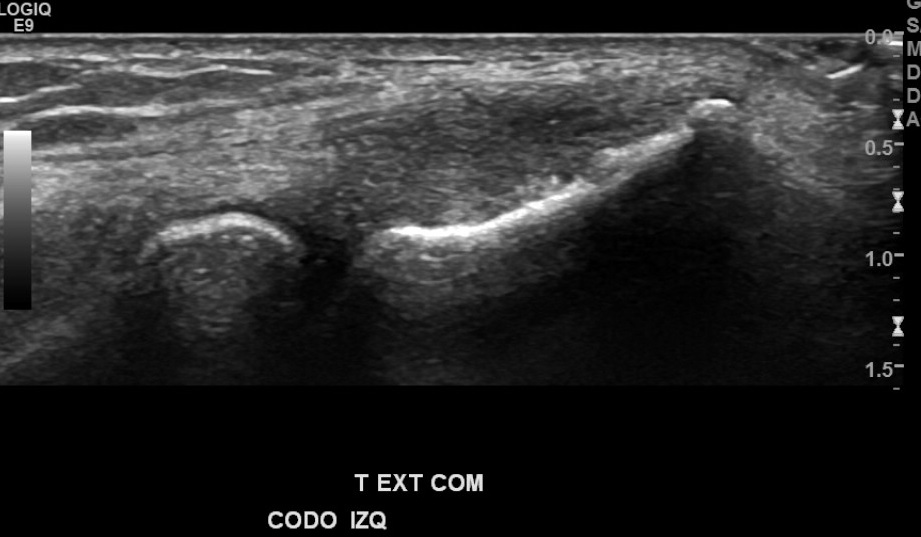

Antecedentes: chequeo por marcado dolor de región epicondilo lateral de codo izquierdo, mayor hace 1 mes aprox., por esfuerzo laboral de EESS, sin trauma.

Hallazgos: marcada heterogeneidad de tendón extensor común izquierdo, con foco de desgarro de espesor y ancho parcial en su espesor, con hiperemia al doppler color.